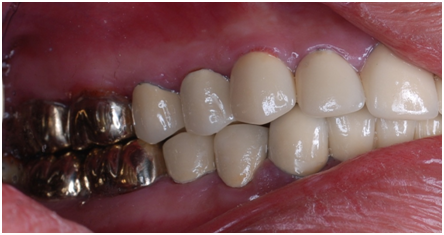

A 22 Yemeni male patient presented to the College of Dentistry clinics at the University of Dammam seeking cosmetic treatment with a chief complaint “I want to improve the way my teeth look " He reported no significant medical history. Patient has never been into the dental clinic. He stated his deciduas teeth were normal and his whole village complains of darkened teeth (brownish). A panoramic x-ray (Figure 1), intraoral pictures (Figures 2−6) as well as study casts were taken to diagnose the case (Figure 7). Upon examination, the patient was found to suffer from severely generalized discoloration of permanent teeth and moderate dental attrition resulting in shortening of the vertical dimension of occlusion (VDO). A class I occlusion with class I canine relation was present, with an over-bite of 4mm and an overjet of 4mm. The upper lip seems stretched with dropping mouth angles. The patient suffers from generalized marginal chronic gingivitis with no mobility or furcation involvement noticed. The treatment plan started with plaque control measures were conducted as well as patient education. The patient's esthetic problem caused by Fluorosis both teeth staining and facial appearance and occlusion. The treatment options available range from bleaching, porcelain veneers, full coverage ceramic crowns or porcelain fused to metal crowns. Due to the Fluorosis severity, the bond strength of the adhesive agent was questionable that eliminated the veneers option. Bleaching when tried had minimal effects. Finally, porcelain-fused to metal (PFM) crowns were selected to restore esthetics of anterior teeth, while posterior gold crowns were chosen to raise the occlusion posterior by 2mm. Treatment options were discussed with the patient who consents to the treatment plan.

Figure 5 Pre op left side.

Figure 6 Pre op right side.

Esthetic, phonetics and occlusion were checked after cementation the temporary crowns with temporary (Pro. Temp) luting agent. To avoid any functional problems, the patient was instructed to give the temporaries a period of trial for 2 weeks. Intra occlusal relationship was repeated at this stage again. When the patient reported no discomfort, the final crowns were constructed. Final crowns were cemented using resin composite (Rely X Unicem) luting agent. Teeth restored were # 2, 3, 4, 5, 6, 7, 8, 9,10, 11, 12, 13, 14, 15,18, 19, 20, 21, 22, 23, 24, 25, 26, 27, 28, 29, 30 and 31. Postoperative pictures, x-rays, and impressions were taken (Figure 9−19). The case had a good prognosis considering the patient, good general health and proper attitude toward his oral hinging reported during the maintenance and treatment phases. The periodontium is in functional health status, using gold alloys to restore posterior teeth as well as porcelain-fused to metal crowns to restore anterior teeth conserve tooth structures by minimizing the amount of tooth structure to be cut.